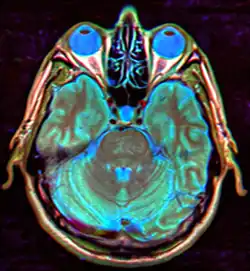

| MRI of Empty Sella | |

| Diagnostic method | MRI, CT scan[1] |

Empty sella syndrome is the condition when the pituitary gland shrinks or becomes flattened, filling the sella turcica with cerebrospinal fluid instead of the normal pituitary.[2] It can be discovered as part of the diagnostic workup of pituitary disorders, or as an incidental finding when imaging the brain.[1]